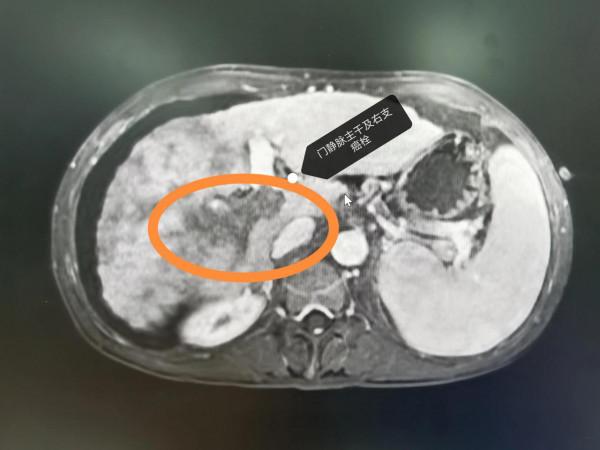

晚期肝癌的病人也不要輕易放棄!近2-3年,晚期肝癌的治療獲得了較大的突破,介入治療+靶向藥+PD1的治療組合,大部分情況下可以取得不錯的治療效果。這是一例非常晚期的肝癌病人,這要是在2-3年前,估計就是勸病人回家,該吃吃該喝喝,預計不會超過3個月的生存期。本例患者巨塊型肝癌合併下腔靜脈癌栓(下腔靜脈幾乎完全堵塞並臨近心房口了)及門靜脈主幹及右支癌栓的病人,經過2次的介入治療(肝動脈灌注化療術(HAIC)後,病灶明顯的縮小,癌栓明顯的消退,腫瘤指標直線下降,整個人的精神狀態持續好轉,未來可期。